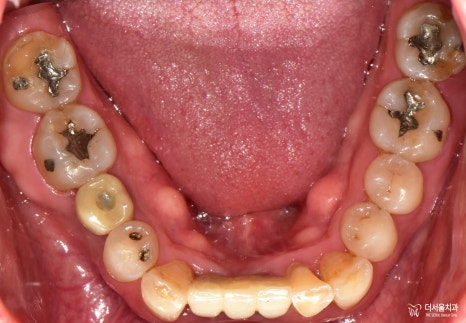

내원 당시 구강 속을 살펴보면

잇몸이 붓고 내려가 있으며

떨어져버린 어금니가 있고,

여기저기 많이 닳아있으며

아예 상아질이 드러난 것을

문정동치과 에서 체크할 수 있었는데요.

우선은 아래 이가 흔들려요 라는

문제의 부분을 먼저 해결해드리려

발치 후 임플란트를 해드립니다.

문정동치과 에서

잇몸치료를 병행하며,

임플란트 뼈이식으로

앞니, 어금니 보철 식립을

해드린 결과입니다.

치열이 좀 비뚤어져 있는 것은

아쉽긴 합니다만,

처음 상태와 비교해봤을때,

많이 개선된 것을 확인할 수 있었습니다.